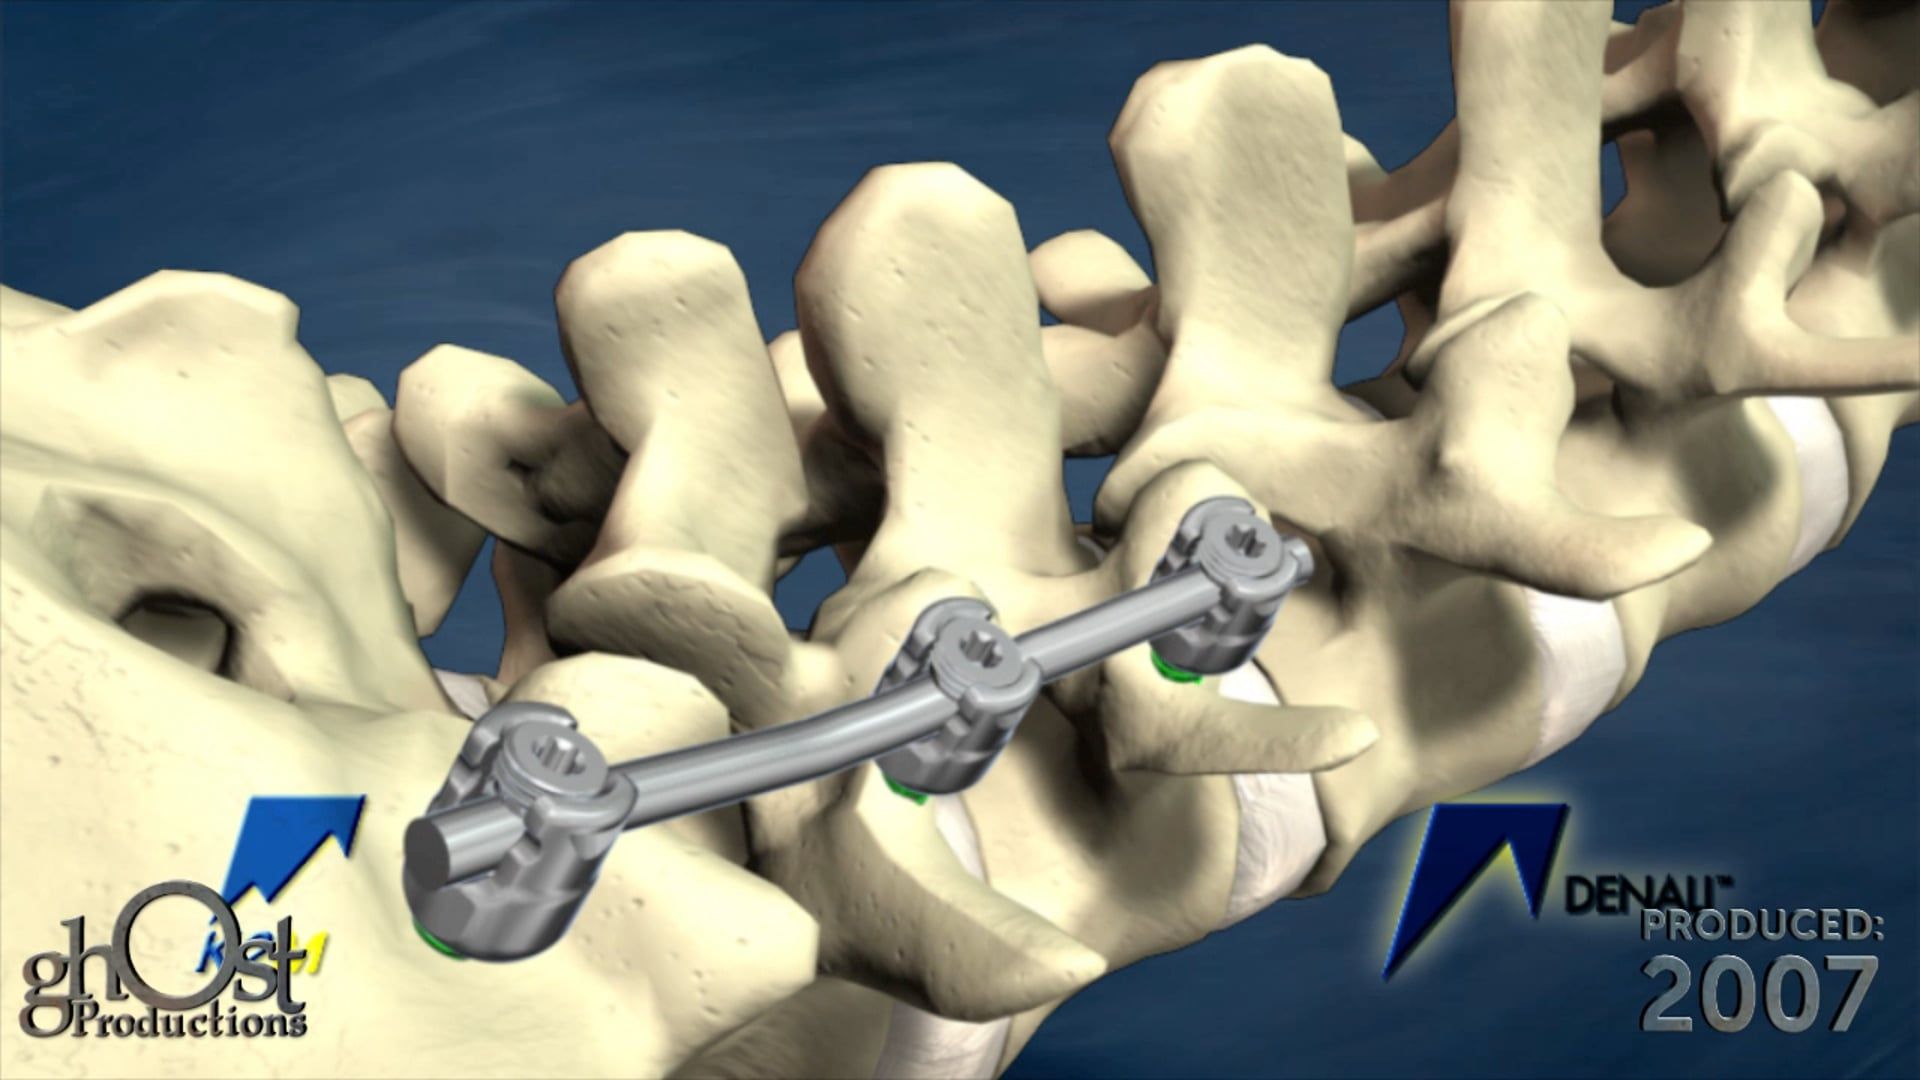

Ghost Productions' animation showcases the Keo Brace, a revolutionary device for Carpal Tunnel Syndrome treatment, providing support to the wrist and reducing pressure on the median nerve. Medically accurate and informative, it's a must-see for healthcare professionals and patients.

Ghost Productions has produced a visually stunning animation that highlights the Keo Brace, a revolutionary device used in the treatment of Carpal Tunnel Syndrome. This video showcases the Keo Brace's unique design and its ability to alleviate the symptoms of Carpal Tunnel Syndrome by providing support to the wrist and reducing pressure on the median nerve. The animation is medically accurate and provides a detailed explanation of how the Keo Brace works, making it an invaluable resource for healthcare professionals and patients alike. This video is a must-see for anyone interested in the latest advancements in the treatment of Carpal Tunnel Syndrome.

The animations showcased by Ghost Medical are intended solely to demonstrate our portfolio work and are not intended to be labeled as reliable FDA claims in the healthcare market. Surgeons and healthcare professionals should exercise caution and conduct their own research before relying solely on the information presented in the animations. Please be aware that while our animations strive to accurately represent medical concepts and technologies, they may not always reflect the current state of the medical industry.